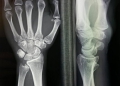

Clinical case : Patient of 30 years, young female, with severe pain in the Druj.

thank you to give me your opinion, Patient of 30 years, young female, with severe pain in the Druj.

Congenital Madelung disease,

isolated osteoarthritis Druj,

almost normal range of motion,

Decreasing of strength.

I see an incongruent DRUJ. I would do a Sauve Kapandji procedure with proximal stump stabilization.

I don’t think that it is a Madelung deformity.

It is not a Madelung deformity but definitely a malformation of the DRUJ. I have performed ulnar shortening on a couple of these with this special configuration of the DRUJ and early OA with very good result. 2mm of shortening is enough. I think the reason for the success is the deloading of the DRUJ which in this case is a combination of ulnar minus variance and Tolat type II joint with impaction between ulnar head and proximal lip of sigmoid notch.

This is no Madelung deformity. The painful. discongruent DRU can best treated by an arthrodesis( Sauvé-Kapandji) in the end an DRU prosthesis

obvious degenerative DRUG due to malformation by severe ulna minus probably mild Madelung.